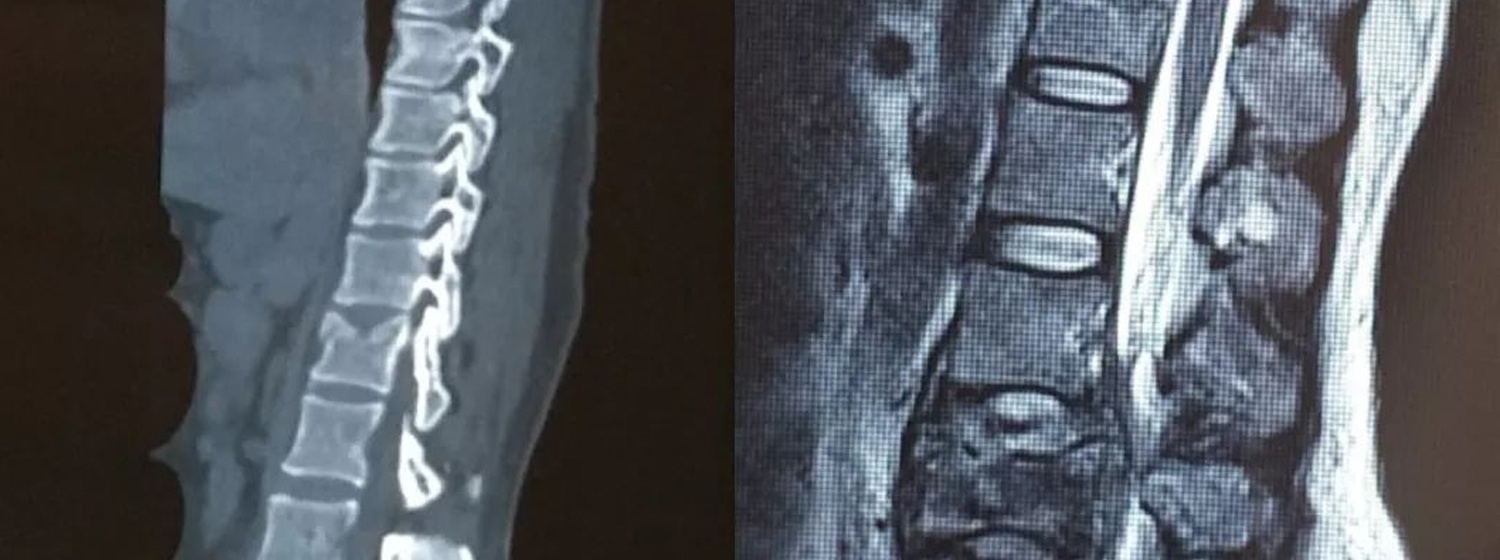

去年11月,龙泉的张大爷骑电瓶车时不慎摔倒。受伤后张大爷感觉颈部疼痛难忍……

突发双腿麻木、大小便失禁,一查原来是这个疾病。65岁的童大伯突然出现双脚麻木的情况……